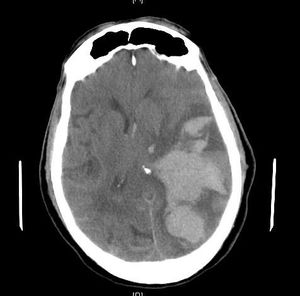

뇌탈출은 뇌 조직이 두개골 내에서 비정상적으로 이동하는 심각한 상태로, 뇌부종, 혈종, 뇌졸중, 뇌종양, 중추신경계 감염 등이 원인이다. 뇌탈출은 발생 부위와 방향에 따라 여러 유형으로 분류되며, 해마, 중심성, 대상회, 두개골, 중뇌덮개, 소뇌편도 등의 탈출이 있다. 증상으로는 비정상적인 자세, 의식 저하, 동공 변화, 구토, 두통, 발작, 쿠싱 삼징후 등이 나타나며, 뇌 기능 상실로 심혈관 및 폐 증상이 나타날 수 있다. 진단은 CT 스캔과 MRI를 통해 이루어지며, 치료는 원인 질환 제거와 감압 개두술을 포함한다. 뇌탈출은 심각한 장애나 사망을 초래할 수 있으며, 신경학적 회복의 예후는 좋지 않다.

5. 진단

뇌 탈출은 임상적 증상과 함께 CT, MRI 등 영상 검사를 통해 진단한다. 후두대공 헤르니아(대공헤르니아)는 소뇌 종양이나 출혈로 인해 천막 하강의 압력이 상승하고, 소뇌편도가 아래쪽으로 밀려나 대후두공(대공) 안으로 끼어든 상태이다. 천막상 병변이 진행되면 천막절흔헤르니아를 일으키고, 추가적으로 압력이 아래쪽으로 발생하기도 하므로, 가장 긴급한 처치가 필요하다.[1]

5. 1. MRI

후두대공 헤르니아, 대공헤르니아라고도 불리는 소뇌편도헤르니아는 MRI를 통해 뇌 구조를 더 자세하게 확인하여 진단할 수 있다. 특히 MRI는 키아리 기형 등 특정 유형의 뇌 탈출 진단에 유용하다.6. 치료

뇌탈출은 응급 상황이며, 신속한 치료가 필요하다. 뇌탈출은 심각한 장애나 사망을 초래할 수 있다. 실제로 CT 스캔에서 뇌탈출이 확인되면 신경 기능의 의미 있는 회복에 대한 예후가 좋지 않다.[2] 환자는 압력을 유발하는 병변과 같은 쪽에 마비가 올 수 있고, 뇌탈출로 인한 뇌 부위 손상은 병변과 반대쪽에 마비를 일으킬 수 있다.[11] 중뇌의 망상 활성계 손상은 혼수상태를 초래하며,[11] 연수의 심혈관 호흡 중추 손상은 호흡 정지와 (이차적으로) 심장 정지를 유발한다.[11] 해당 증후군과 관련된 뇌 과민성의 장기적인 외상 후 기간 동안 신경 보호제 사용에 대한 연구가 진행 중이다.[17]

뇌 탈출은 심각한 장애나 사망을 초래할 수 있다. CT 스캔에서 뇌 탈출이 확인되면 신경 기능의 의미 있는 회복에 대한 예후가 좋지 않은 경우가 많다.[2] 환자는 압력을 유발하는 병변과 같은 쪽에 마비가 올 수 있고, 뇌 탈출로 인한 뇌 부위 손상은 병변과 반대쪽에 마비를 일으킬 수 있다.[11] 중뇌의 망상 활성계 손상은 혼수상태를, 연수의 심혈관 호흡 중추 손상은 호흡 정지와 심장 정지를 유발한다.[11] 현재 뇌 과민성의 장기적인 외상 후 기간 동안 신경 보호제 사용에 대한 연구가 진행 중이다.[17]